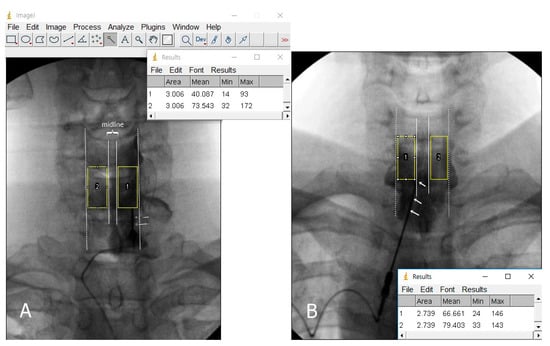

2.3. Image and Data Analysis

| Brightness ratio | 1.47 (1.17–1.94) | 1.17 (1.10–1.41) | 1.91 (1.50–2.35) | <0.001 1 |

| Brightness ratio | 1.47 (1.17–1.94) | 1.66 (1.41–2.10) | 1.16 (1.09–1.26) | <0.001 1 |